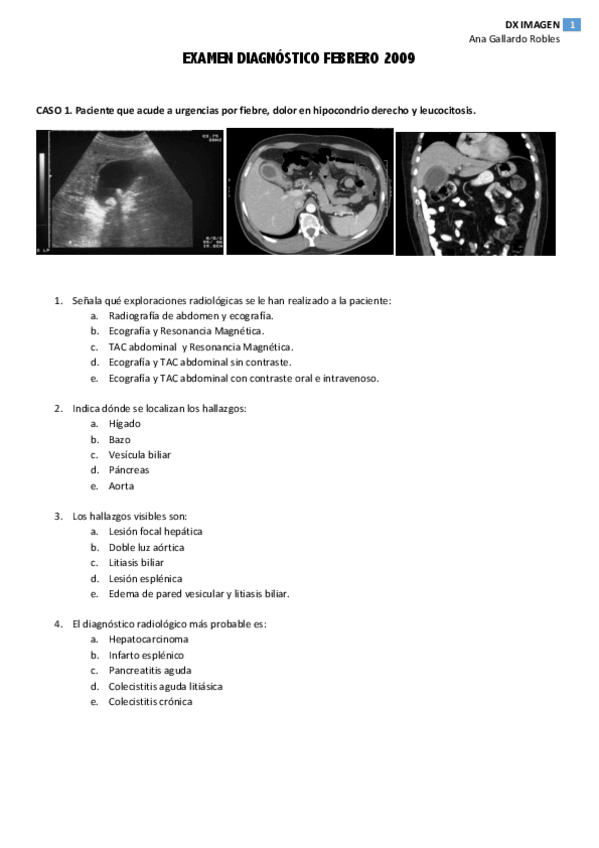

Exámenes - 2009-2010 Imágenes.pdf

29 páginas